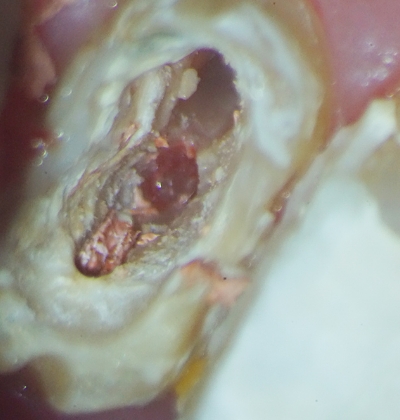

マイクロスコープを用いた精密な治療

歯の根の中は直接肉眼で見ることが不可能な上に、歯の神経が通っている根管は細く、複雑に枝分かれしています。

そんな細く複雑な形状をした根管から、神経をきれいに取り出し、洗浄・消毒するには細部までしっかりと捉える視野が欠かせません。

そのために当院では、感染部位の取り残しや、歯の削り過ぎがないようにマイクロスコープを使用して治療を行っています。

マイクロスコープでは最大で肉眼の20倍まで拡大して見ることができるため、肉眼での治療よりはるかに精密な治療を可能にしています。

症例紹介

主訴

歯肉が腫れ、痛みがあるとのことで来院

治療内容

根管治療

患者さまの年齢・性別

29歳・男性

治療期間

約1か月

費用

保険適用

詳細

本来開いていない箇所に穴が開いてしまっているパーフォレーションと呼ばれる状態であることを確認しました。

おそらく他院で使用したであろう根管充填材が残ってしまっていたので、

マイクロスコープを用いて隅々まで取り除き根管内をきれいにした状態で、再度埋めていく治療を行いました。